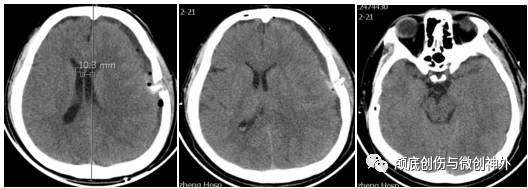

头颅CT:

头颅MRI平扫:

1.左侧额颞颞亚急性硬膜下血肿;

2.颅内高压。

3. 影像学提示:中线移位大于1cm,左侧颞叶沟回压迫脑干,左侧顶部皮层脑沟变窄,脑回增宽,回流静脉曲张。